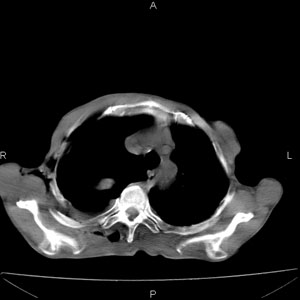

患者男,77岁,于3日前从树上摔下,头部查ct示蛛血,硬膜下出血,上腹部ct未见明显异常,右侧胸腔积液,左侧如常。肺部拍片示右侧肋骨多发骨折住院后今日来查肺部ct,我看到的是1。右侧胸腔血气胸并右肺上叶,中叶压缩性肺不张,2。右肺下叶肺挫伤并多发肋骨骨折,肌内及皮下积气3。左侧少量胸腔积液,我想请教的是3天前左侧胸腔里没有积液今天怎么出现了呢,是什么原因呢?请讨论。